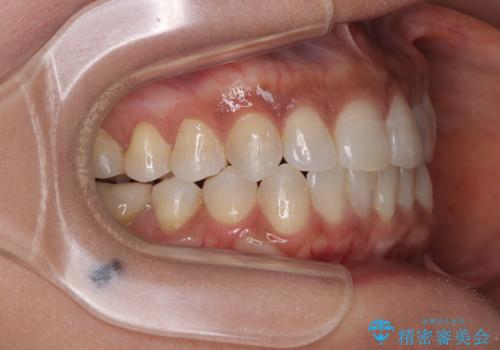

咬合力が非常に強く、治療が進むにつれて上下奥歯が離開してくることが予想されるため、治療途中から上下の顎間ゴムを使用することを理解いただき、インビザラインによる矯正治療を行うこととしました。

咬合力による臼歯離開は顎間ゴムで改善されましたが、それとは別に下顎小臼歯がマウスピースに追従せず、補正のためのゴムかけが必要となりました。

大変なゴムかけ作業を頑張っていただき、無事に治療を終えることができました。